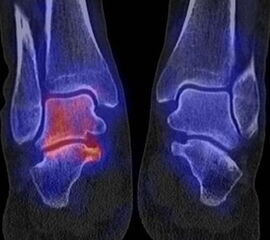

Abbildung 2.1.

Bildbeispiele symptomatische OCL

Zum Lesen der Bildbeschreibung und zur Vollansicht bitte das Bild anklicken. Bild: H. C. Rischke

Abbildung 2.2.

Bilder eines Patienten mit Z. n. mehrfachen Sprunggelenksdistorsionen in der Vergangenheit, besonders heftige Distorsion des linken Sprunggelenkes 5 Wochen vor der Untersuchung. Die SPECT/CT zeigt eine instabile osteochondrale Läsion mit deutlicher Aktivierung.

Abbildung 2.3.

Klärung bei Schmerzen im rechten OSG bei OCL an der medialen Talusschulter. Z. n. OSG-Distorsion vor 2 Jahren und Z. n. OSG-Fraktur / Syndesomosenruptur. Ausgedehnte OCL, hier jedoch kein erhöhter Knochenmetabolismus; lediglich Nachweis einer Stressreaktion im Bereich der Synchondrose eines Os trigonum als Schmerzursache.